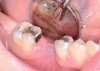

Fig 8. Loss of restoration and subsequent tissue overgrowth from broken abutment screw as shown in the radiograph (Fig 9).

Figure 8

Fig 9. Radiograph depicting fractured screw inside of the implant.

Figure 9

Fractured screws are challenging to retrieve, particularly when they are abutment screws. If the screw head is accessible, a hemostat can be used to remove it. However, when the screw breaks inside the implant (Figure 8 and Figure 9), removal can be highly complicated in order not to damage the implant’s internal threads. Therefore, many implant manufacturers have developed screw-retrieval kits. Because it is critical to be able to visualize the area, magnification using loupes and a surgical microscope may be necessary.8 Additional methods can be used to remove the fractured screw. A ¼ round bur set on a high speed can be used by lightly activating it, touching only the side of the screw. After repeating this technique several times, the screw may be able to be backed out with an explorer tip. Ultrasonic tips with copious irrigation may also dislodge the screw.7,20 In cases in which this fails, a small slot can be made in the head of the screw to back it out.21 If screw threads have been damaged during retrieval, they may be retapped using a tool obtained only from the implant manufacturer.7